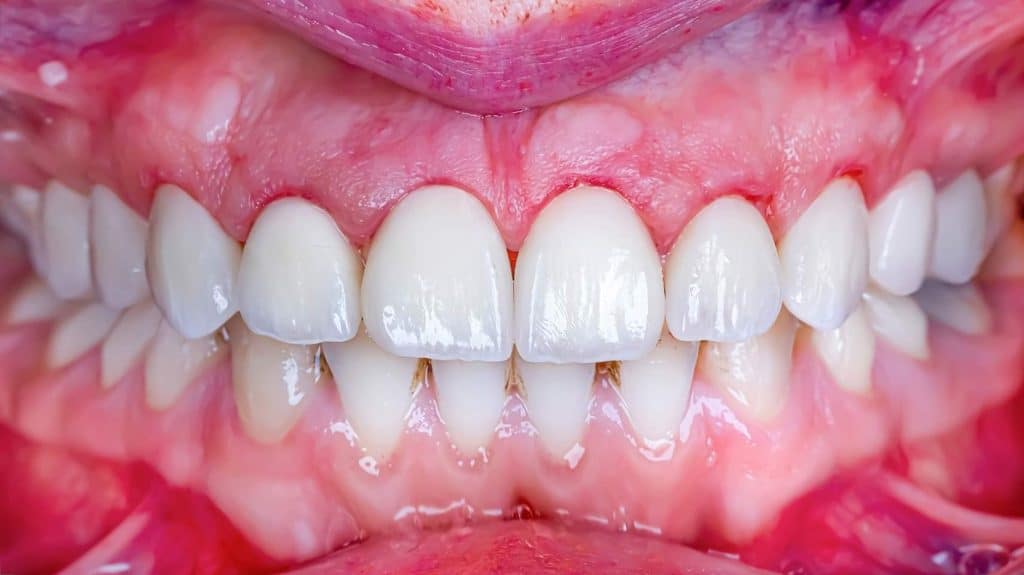

Thus, during clinical examination, it is fundamental to explore the patients’ estimate of dental esthetics. However, some objective parameters can be used to identify the most expressive changes that may compromise oral esthetics. Many characteristics of teeth and gingiva, such as tooth dimension clinical crown width-to-length ratio, color, shape, and gloss, among others, as well as gingival shape, contour, embrasure, zenith, and height (position or level), are part of what is called micro-esthetics. These parameters cannot be analyzed separately, although being very important to result on a pleasant smile (mini esthetics) but in association with a harmonious face (macro-esthetics) to result in good self-esteem (hyper-esthetics).

The tooth- gum interface of both central incisors should be on this line, while the lateral incisors are approximately 1.5 mm below this line.[5] The gingival line is preferably parallel to the occlusal frontal line. The gingival zenith of the homologous teeth should be on the same plane, guaranteeing the symmetry of the dental-gingival composition. Since the long axis of the anterior maxillary teeth is slightly inclined to the distal, the gingival contour does not form a symmetric arch, and the gingival zenith is slightly displaced to the distal side.

The case presented in this case report is for a 27-years-old female patient with a chief complaint of aesthetic correction for her smile. The patient was unhappy with her smile. After clinical examination, there were previous old composite veneering done poorly and incorrectly to close the multiple interdental spacing. After discussing the various treatment options (i.e., orthodontic treatment, direct, or indirect veneers), indirect ceramic veneering was selected. The step-by-step treatment protocol is presented in the images below.